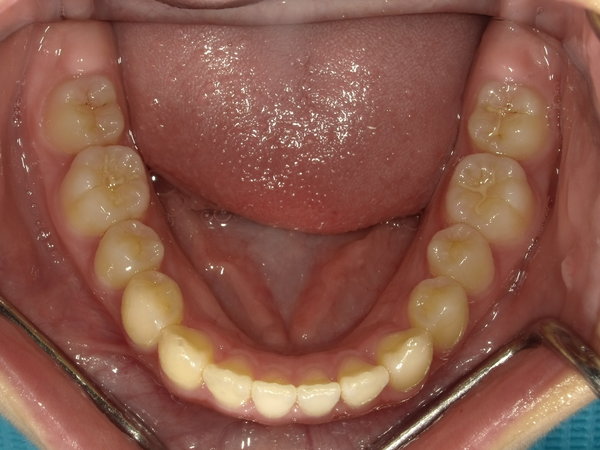

すきっぱ(空隙歯列)CASE5 2023.06.19 10代女性非抜歯〇ご相談内容:上前歯のすきっぱ〇矯正の種類:マウスピース型矯正「インビザラインGO」〇治療期間:14週間〇治療費用:44万円(税込) < すきっぱ(空隙歯列)CASE6すきっぱ(空隙歯列)CASE4 > ブログ記事一覧をみる